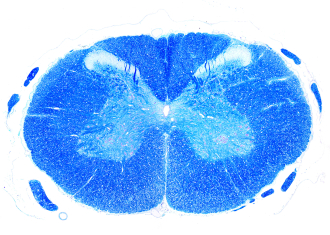

Pokud dojde k poškození mozku, gliové buňky se začnou dělit a putovat k místu poškození – oproti tomu vznik nových neuronů je velmi omezený. Dozvíte se, jak v současném výzkumu z gliových buněk vytváříme nové neurony, jakou roli v tom mají geny a jaký je potenciál v léčbě neurodegenerativních onemocnění.